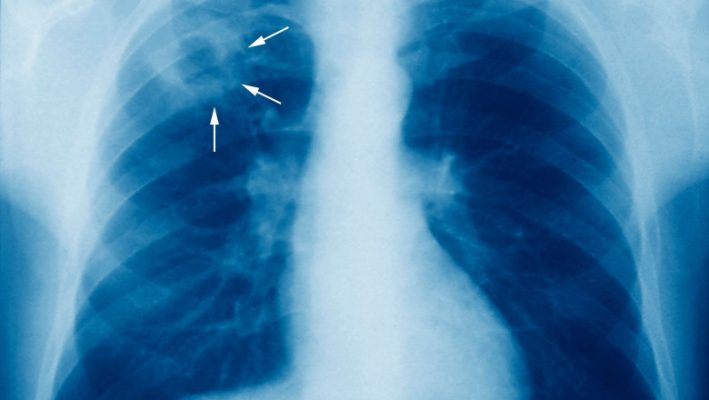

Deși la nivel național România depune eforturi considerabile pentru a se desprinde de titlul de țară cu cea mai mare incidență a tuberculozei din Uniunea Europeană, dinamica locală din județul Hunedoara oferă o perspectivă nuanțată asupra luptei cu bacilul Koch. Datele recente furnizate de dispensarele de specialitate indică o evoluție fluctuantă a bolii, marcată de o scădere încurajatoare a cazurilor noi în ultimul an, dar și de o persistență a recidivelor care pune sub lupă importanța aderenței la tratament.

Analizând parcursul ultimilor ani, observăm că Hunedoara a traversat perioade de presiune crescută asupra sistemului de sănătate publică. Dacă în intervalul 2021-2023 s-a înregistrat o pantă ascendentă, culminând cu un vârf de 147 de îmbolnăviri noi, statisticile pentru anul 2025 aduc o rază de optimism, numărul acestora coborând la 87 de cazuri. Această diminuare semnificativă sugerează o eficiență sporită a programelor de screening și o mai bună conștientizare în rândul populației, însă tabloul clinic rămâne incomplet fără monitorizarea atentă a cazurilor readmise.

Recidivele reprezintă, în continuare, o provocare constantă pentru medicii hunedoreni, menținându-se la o medie relativ stabilă de aproximativ 26 de cazuri anual. Această cifră subliniază faptul că tuberculoza nu este doar o problemă medicală, ci și una socială, unde abandonul terapeutic sau diagnosticarea târzie pot transforma o boală tratabilă într-o amenințare persistentă. Într-un context regional unde formele rezistente la tratament încep să câștige teren, rigurozitatea cu care pacienții urmează schemele de medicație devine factorul decisiv între vindecare și cronicizare.